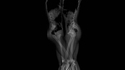

Des rayons X montrent la quantité qu'un hamster peut stocker